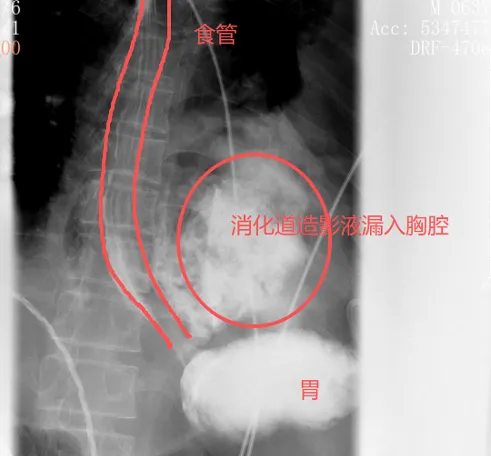

很快,口服钡餐的效力印证了他的判断:钡剂从食谈下段的裂口处大批漏出,平直过问了左侧胸腔。

红圈区域是食品残渣、消化液破入食管